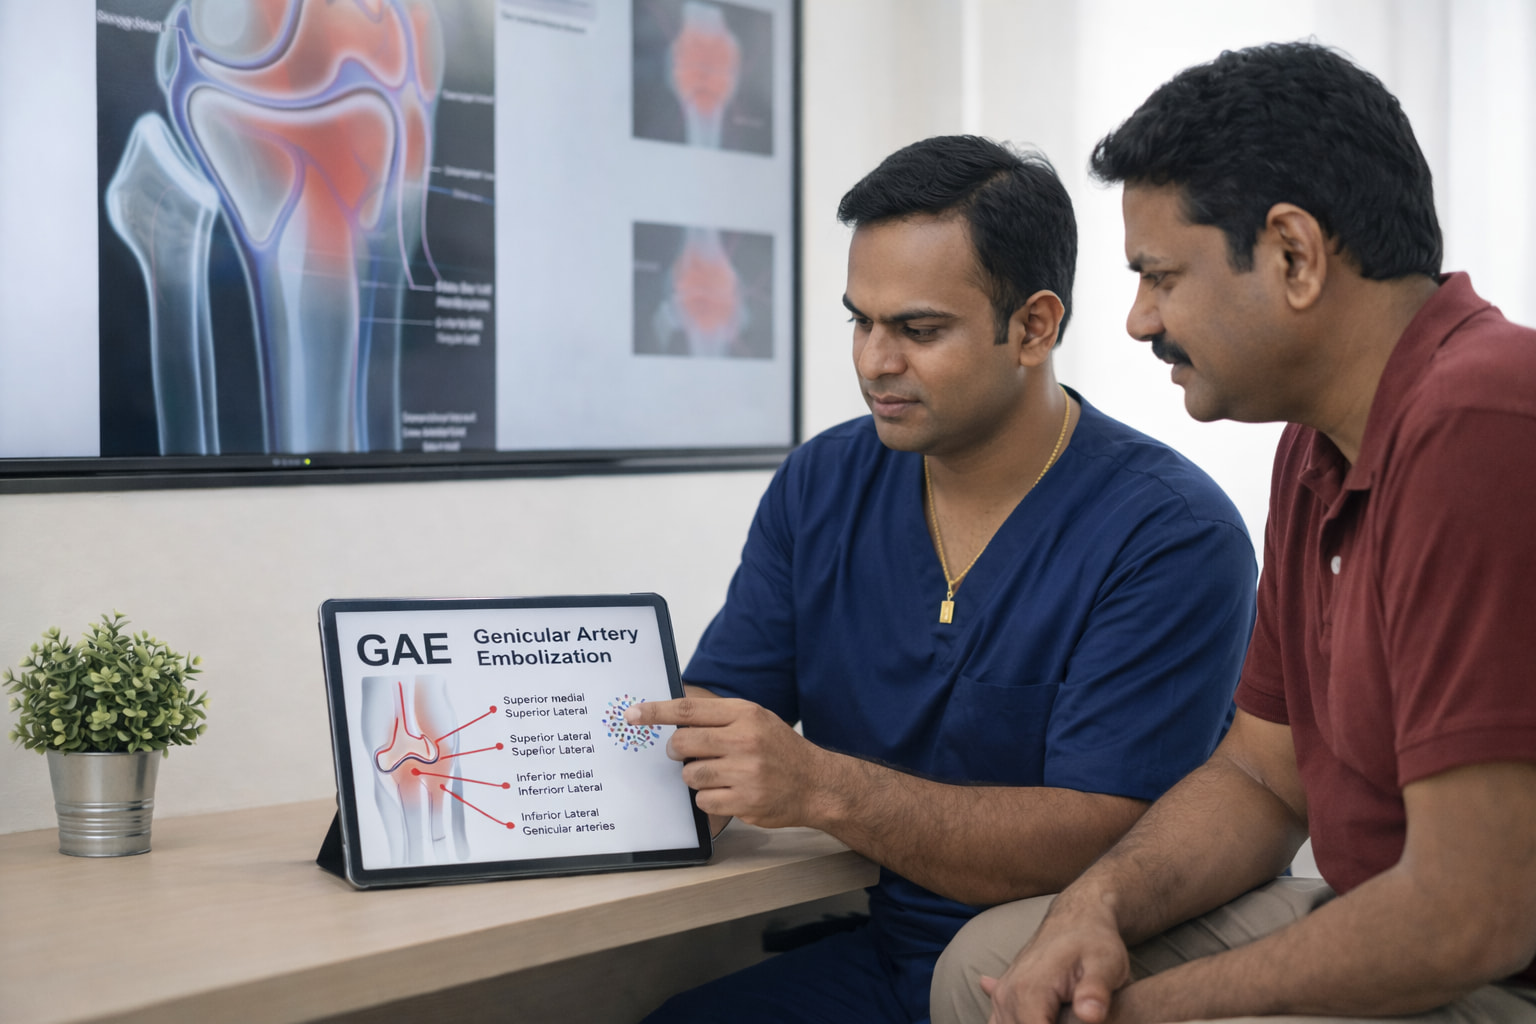

🩺 What Is Genicular Nerve Ablation?

Using thermal energy (Radiofrequency Ablation (RFA) or cold energy (Cryoablation), to “turn off” the specific nerves responsible for transmitting pain signals from the knee joint to the brain. By interrupting these signals, patients can experience long-term pain relief and improved mobility without the need for invasive joint replacement.

🎯 How It Works: Silencing Pain Signals

The procedure is performed in two precise stages to ensure the best possible outcome:

- The Diagnostic Block: To confirm that the genicular nerves are the primary source of your pain, a small amount of local anesthetic is injected near the nerves. If you experience significant temporary relief, you are a candidate for the ablation.

- Image Guidance: Using real-time X-ray (fluoroscopy), Dr. Ram precisely positions specialized needles near the sensory nerves of the knee.

- Thermal/Cold Ablation: A small amount of radiofrequency/cold energy is passed through the needle, creating a heat/ice lesion on the nerve.

- Signal Interruption: This “stuns” the nerve, preventing it from sending pain messages. The nerve remains intact, but its ability to transmit pain is deactivated.